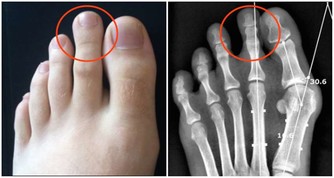

2、戒菸限酒

經常吸煙不僅會提高罹患肺癌、哮喘的風險,還會顯著降低人體免疫力。而酗酒除會引發酒精中毒外,同樣會削弱人體的免疫功能。